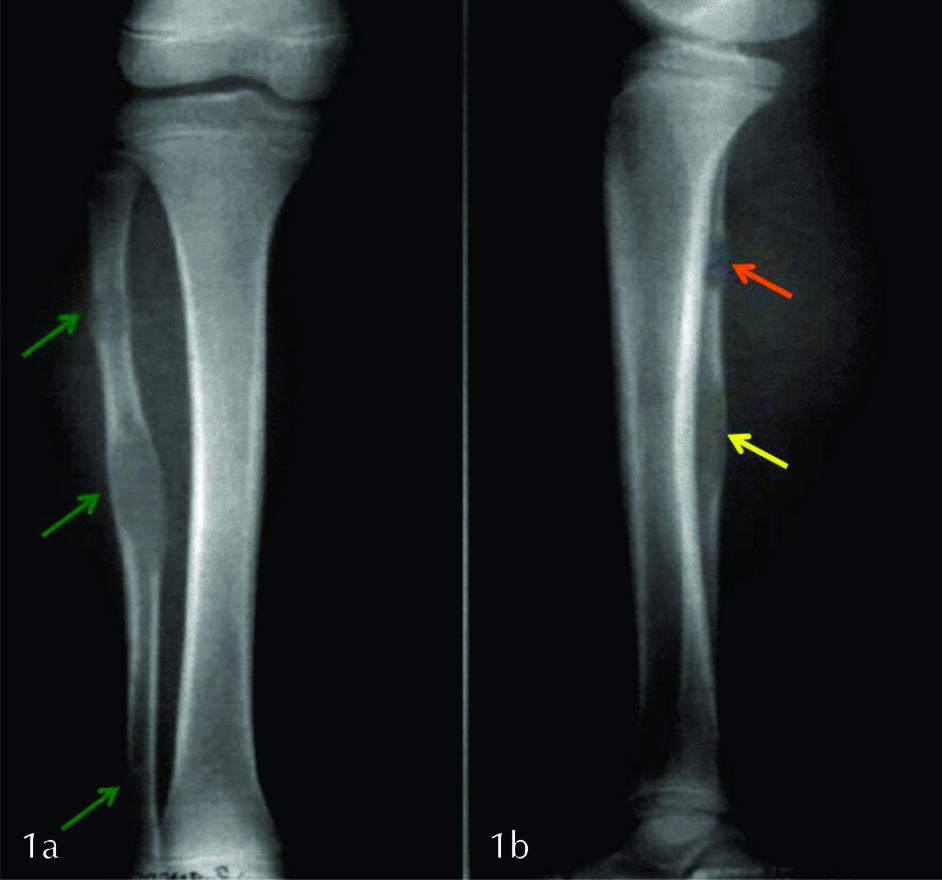

Se solicitó radiografía simple de pierna derecha en proyección frontal y de perfil (Ver fig. 1 y 2), que se completó con TC sin contraste a pedido del traumatólogo tratante (Ver fig. 3).

Figura 1

Radiografía de pierna derecha

a) frente, b) perfil.

Se identifican tres lesiones líticas (flechas verdes) diafisarias y metafiso diafisarias, localizadas en la medular del tercio superior, medio e inferior del peroné. Presentan bordes geográficos sin anillo esclerótico y zona de transición estrecha (lesiones tipo 1b). Véase como expanden y adelgazan la cortical (flecha amarilla). No posee matriz radiológicamente visible, componente de partes blandas ni compromiso articular por este método. La lesión superior presenta un trazo horizontal esclerótico que podría corresponder a fractura evolucionada (flecha naranja).

Figura 2

Radiografía de frente con aumento del área de interés.

La lesión proximal presentaba reacción perióstica de tipo continua (flecha verde) en asociación a un trazo esclerótico en relación a factura patológica evolucionada (flecha naranja). El resto de las lesiones no presentaban reacción perióstica.